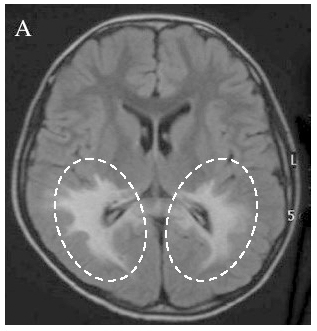

極長鎖脂肪酸は一部の細胞で利用される一方、大部分の細胞では、極長鎖脂肪酸を運ぶ特殊な輸送タンパク質の働きによって分解されます。我が国の難病に指定される副腎白質ジストロフィー(指定難病20)は、この輸送タンパク質の機能が遺伝的に不全であるために生じます。副腎白質ジストロフィーは、脳の中の炎症反応を伴う進行性の脱髄症状※6(図2)や、副腎機能の不全を特徴とする疾患です。

図2 副腎白質ジストロフィー患者のMRI画像

副腎白質ジストロフィー患者(大脳型)の脳では、脱髄領域(図の点線領域)が認められる。(岐阜大学ALD&ペルオキシソーム病ホームページより許可を得て転載)